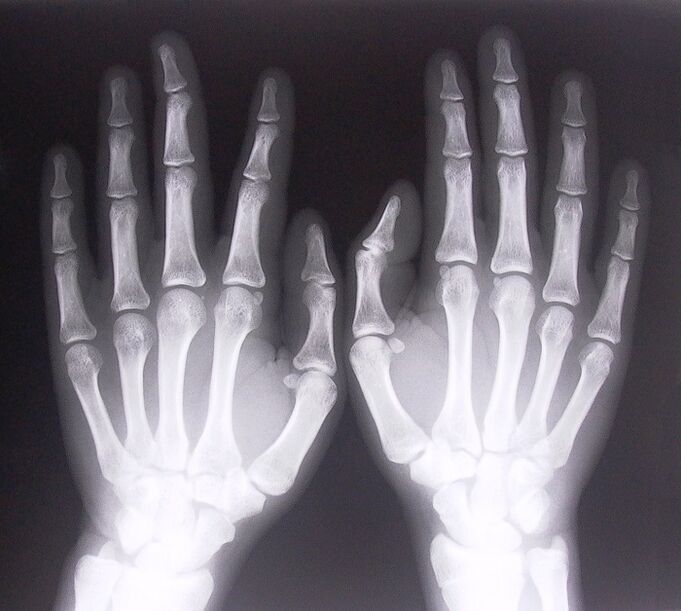

Wie diagnostiziert man?

Um mit der Behandlung von Schmerzen in den Fingergelenken zu beginnen, ist es notwendig, richtig zu bestimmen, welche Krankheit sie verursacht hat. Um festzustellen, an welcher Art von Krankheit eine Person leidet, die beim Beugen der Arme Gelenkschmerzen verspürt, empfehlen Ärzte die folgenden Verfahren:

- Machen Sie Röntgenaufnahmen.